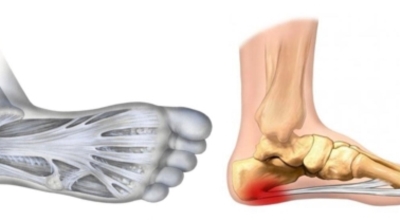

족저 근막이란 발가락 시작지점부터 발뒤꿈치뼈까지 발바닥 전체를 감싸고 있는 두꺼운 막을 말합니다. 족저 근막은 발바닥 아치를 지속시켜 발바닥이 지면을 내딛음으로써 발생하는 충격을 흡수하는 중요한 역할을 수행하고 있답니다. 이 족저 근막에 일차적으로 서서히 조직 손상이 일어나고 계속적인 활동으로 말미암아 염증이 커지면서 발 뒤꿈치 부근 통증을 일으키게 되는데 염증은 무리하고 반복적인 동작, 많은 사용으로 마찰에 의해 발생합니다.

족저 근막염은 염증에 의한 손상 및 통증을 유발하는 질환인데요 족저 근막염 증상은 일반적인 발뒤꿈치 통증 하글런드 병변의 기형으로 알려져 있으고 아킬레스 건과 관련이 깊다고 합니다. 특히 근육이 덜 풀린 아침 시간 대는 보행 시 날카롭고 바늘로 찌르는 듯한 심한 통증을 느끼게 된다고 합니다. 하지만 아침 시간 대를 지나 오후에 접어들면서 어느 정도 통증은 서서히 감소하기 시작한다고 하는데요 초기 증상이 나타난다면 꼭 전문의를 찾아 조기치료하는 것이 바람직합니다.